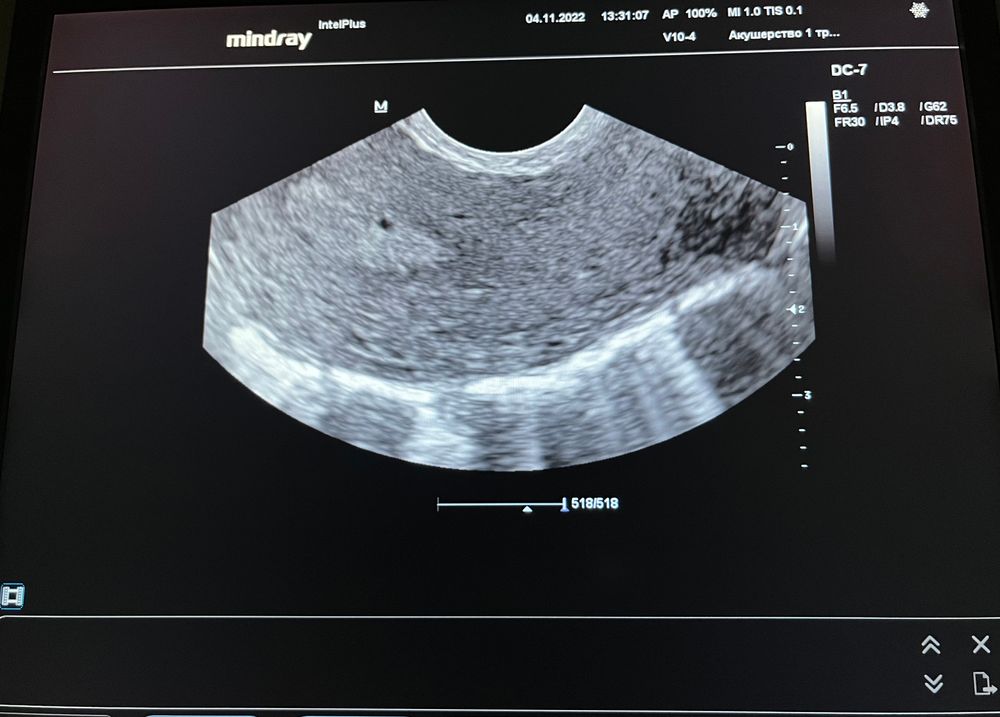

фото узи 4.11.2022 и 10.11.2022 разница неделя, пя вообще не выросло…((( хгч растет… на 10.11.2022 было 1338 ед.

А размеры где? Мне кажется растет и на втором УЗИ даже содержимое ПЯ есть, только снимки не корректные... Там же масштаб есть....

Александра , мне кажется первое узи не информативно вообще, не могли ничего там измерить и найти при таких анализах.... Переделать хгч пару раз через день и УЗИ через неделю, дай Бог, чтоб все было хорошо 😇 на втором УЗИ мне кажется ПЯ не пустое🙏🙏🙏

Действительно, на первом узи скорее всего не пя было. А что то другое. При хгч 147 оно не визуализируется. Узист там не пойми чего нашёл. Не берите первое узи во внимание

Хгч может расти и при зб, к сожалению, но у вас, во-первых, размеры не указаны, во-вторых, разные аппараты (или мне кажется?). Если так, то не информативно

София, верно, аппараты разные,

на первом узи (платная клиника) сказали размер 2,3 мм, а на втором узи (поликлиника по полису) доктор сказала аппарат даже размер не считает…